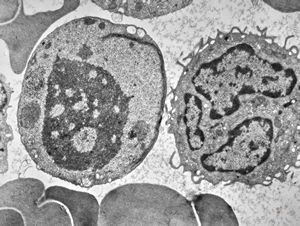

F,50y. | blood … lymphocyte and thrombocyte

blood - neutrophilic granulocyte

F,61y. | blood - neutrophilic granulocyte